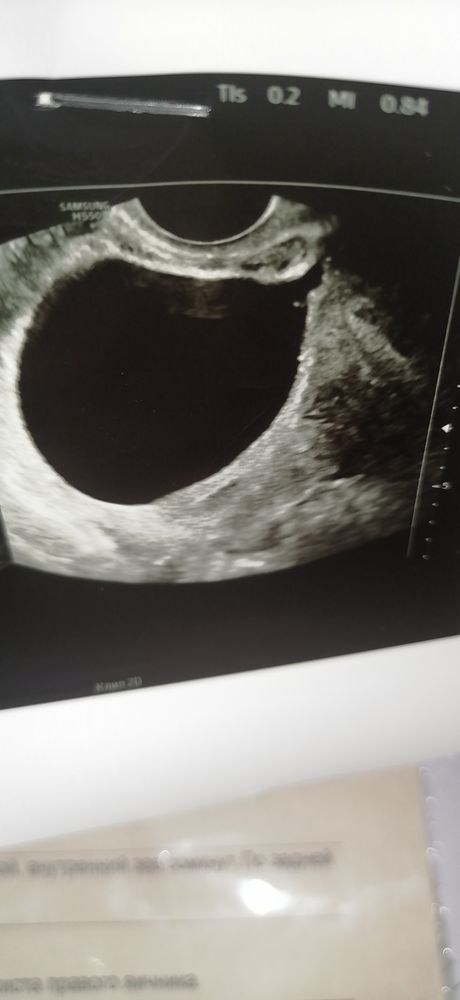

Александра Катаева, здесь разве что то есть? Это узи 13 числа, ПЯ 11мм, ЖМ 3,9мм

Екатерина, честно говоря, здесь не очень удачный ракрус для оценки... То ли доктор слишком увеличил... то ли срез не тот. Но, наверняка, были и другие. Думаю, самое разумное - верить протоколу, настраиваться на хорошее и ждать четверга. Ждать и догонять хуже всего... )) Но там уж точки над i точно будут расставлены))